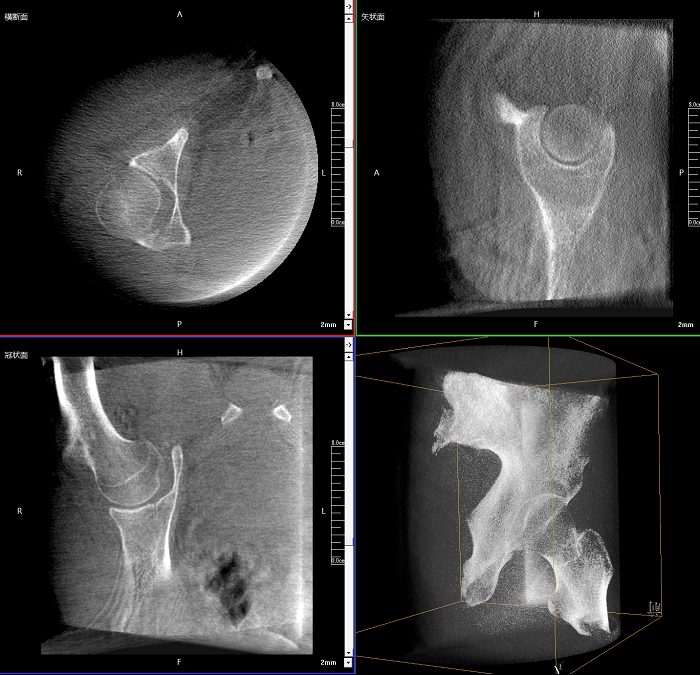

該設(shè)備可進(jìn)行快速的術(shù)中三維掃描,生成類(lèi)CT斷層圖像和立體3D圖像,保障植入物置入效果。廣泛適用于骨科、脊柱外科、矯形外科、創(chuàng)傷骨科等其他領(lǐng)域。

●極速成像僅需8秒,從數(shù)據(jù)采集結(jié)束到完成三維重建斷層影像